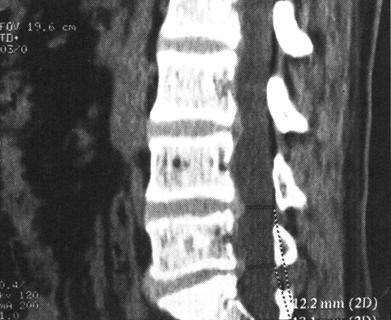

CT在脊柱脊髓损伤中应用很广泛,横断面成像是诊断脊椎骨结构创伤的主要手段,它可显示X线平片不易显示的细微骨折和小关节脱位,并能够很好地显示骨性椎管的情况,可为评价脊髓受压情况提供重要的影像学信息。螺旋CT扫描技术可对患者进行快速连续多部位成像,并支持多平面及三维成像。因而CT扫描对理解脊柱复杂解剖部位,发现细微病变有十分重要的临床意义(图7-4至图7-6)。甚至明显侧弯变形脊柱的冠状面重建亦可通过严格按照脊柱弯曲度改进的软件而获得。单纯轴位扫描很容易漏诊与CT断层面平行的骨折,例如,发生在齿突基部和胸腰水平的创伤,在横断位扫描中不能显示横断水平的骨折线,但在高质量的冠状、矢状和三维的重建图像中显示良好(图7-7至图7-10)。

图7-4 多排螺旋CT重建:沿神经根出口的斜矢状面重建,可显示硬膜囊和神经根管的情况

图7-5 多排螺旋CT重建:冠状面重建,显示硬膜囊和双侧神经根袖

图7-6 多排螺旋CT重建:正中矢状面重建,显示椎体和硬膜囊